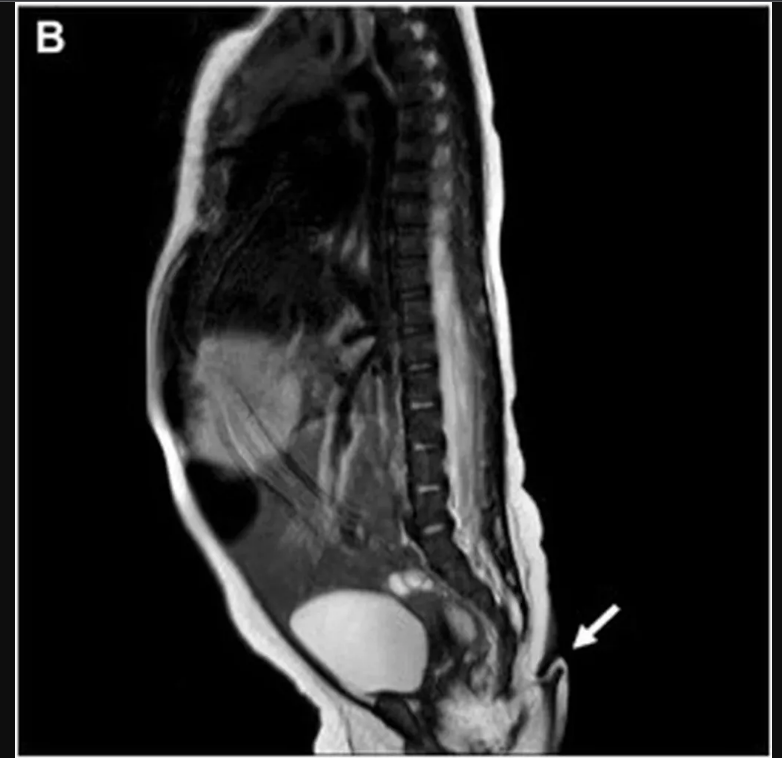

El Journal indicó que, tras hacerle una radiografía, el personal médico no encontró ninguna evidencia de anomalías o estructuras óseas en su interior. La beba tampoco presentó problemas cardíacos o auditivos, malformaciones del tracto urinario, anomalías cerebrales y tampoco malformaciones de la columna.